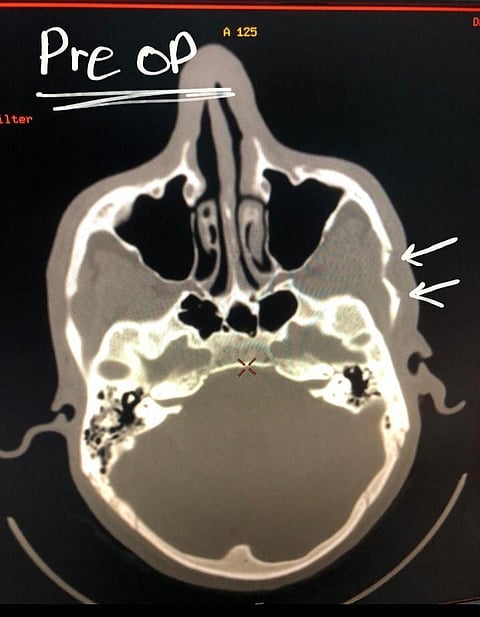

وأوضحت أنه بعد متابعة العلامات الحيوية له فقد ظهرت جميعها طبيعية، فيما كان يشكو من تورم بسيط بالقسم الأيسر من الوجه، وعدم القدرة على فتح الفم، وبعد عمل الأشعة تبين وجود كسور في القوس الصدغي الأيسر.

وأضافت "صحة بيشة" أن الفريق الطبي قام بتجهيز المصاب وإدخاله إلى غرفة العمليات وإجراء العملية الجراحية له بمدخل تجميلي، وتم إرجاع الكسور إلى وضعها الطبيعي، وتم عمل أشعة أخرى، وتبين تلاحم الكسور بشكل جيد، وتحسن في فتح الفم لدى المريض، وخرج من المستشفى وهو بصحة جيدة.